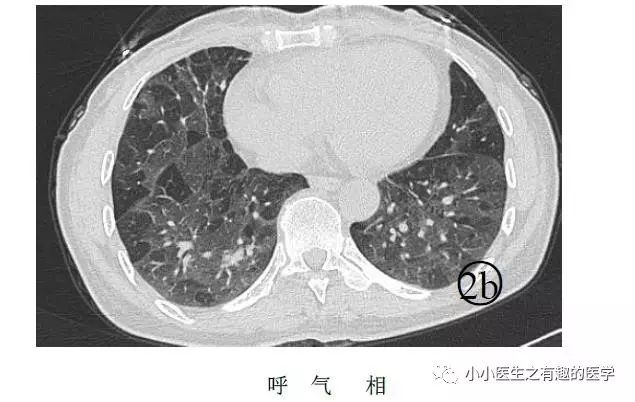

另外,CT发现肺纹理减少,也要警惕肺栓塞。先来说说马赛克。

马赛克征象:由于气道疾病或肺血管性疾病,引起相邻的肺区血液灌注上的差别而出现的不均匀肺密度区,称马赛克灌注。

以图说话,下面都是马赛克,关注了

↓↓↓

如图:

假如CT平扫发现肺部某些地方血管稀疏,灌注不足,千万不要以为没事,有时候,就是肺栓塞,需要警惕。

马赛克,需要警惕肺栓塞,它是肺栓塞的间接表现。并且,在临床中,间断会遇到这样的情况。